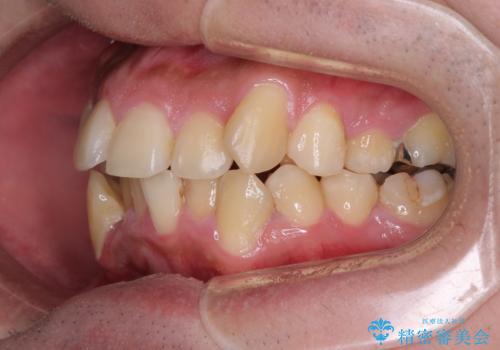

- 八重歯を気にして来院された患者様です。

上下左右の犬歯が八重歯になっており、口元にもやや突出感があるため、上下左右の小臼歯4本を抜歯し、ワイヤー装置にて矯正治療を行うこととしました。